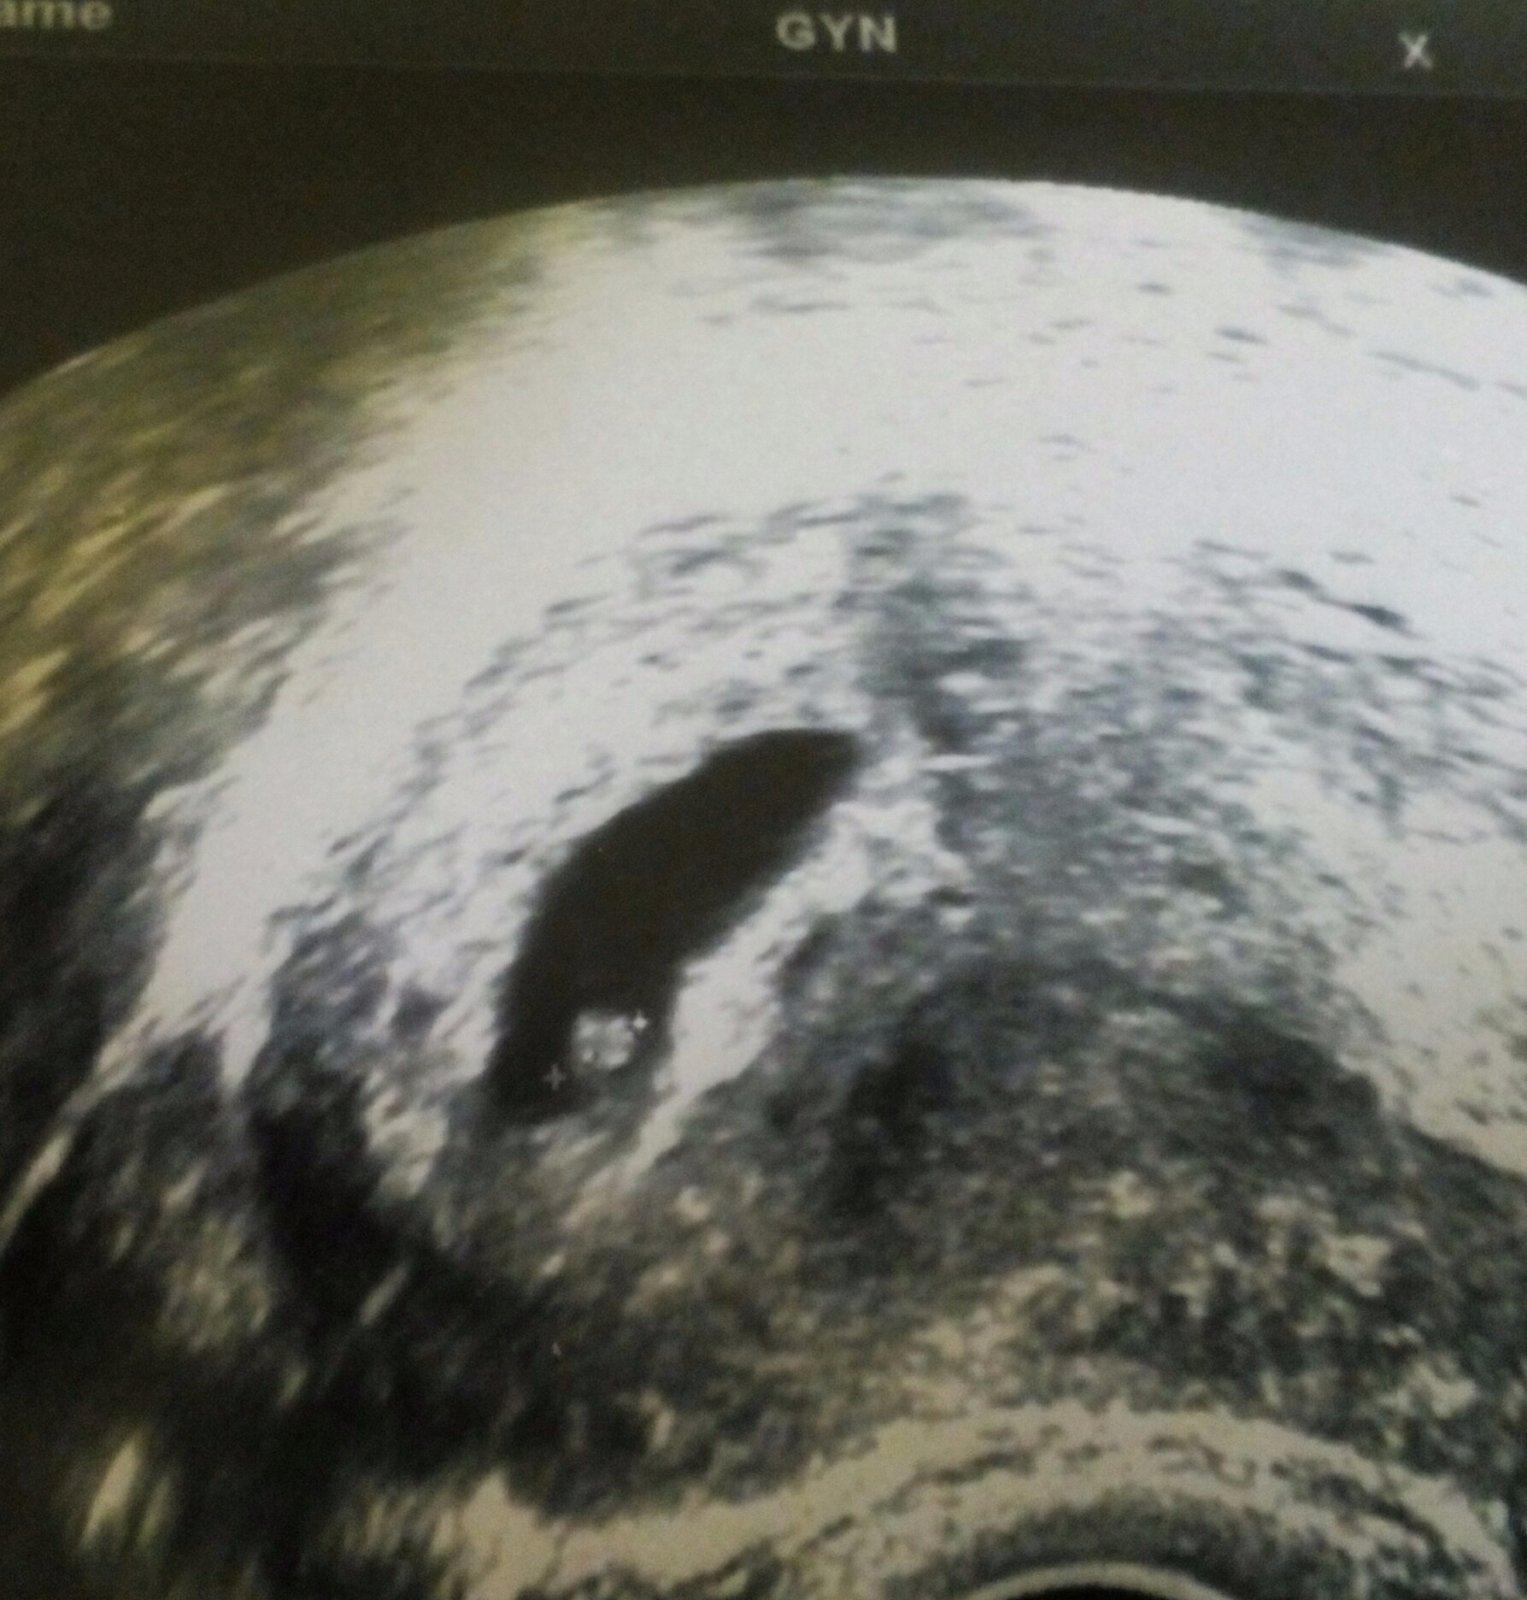

Ahoj holky,pridavam fotecku naseho malinkyho broucka.👶💕 jsme 6+2 a krasne nam bije srdicko😍 foto jsem dostala,protoze jsem byla ted na pohotovosti s tim,ze me boli v krku,nemohu polykat,mam rymu a mota se mi hlava... Tak me zkoukla celou... Nastesti to na antibiotika neni 😇 tak musime odpocivat a cucat pastilky 😊

Jinak fotečka krásná 😉

@bbubble tak má třeba horší UZ,prcek muze byt nekde u steny a hned vidis prd,to bude dobry 🙂